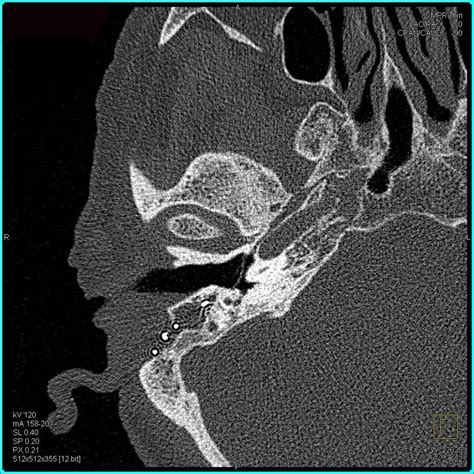

Title: - Imaging Of The Temporal Bone